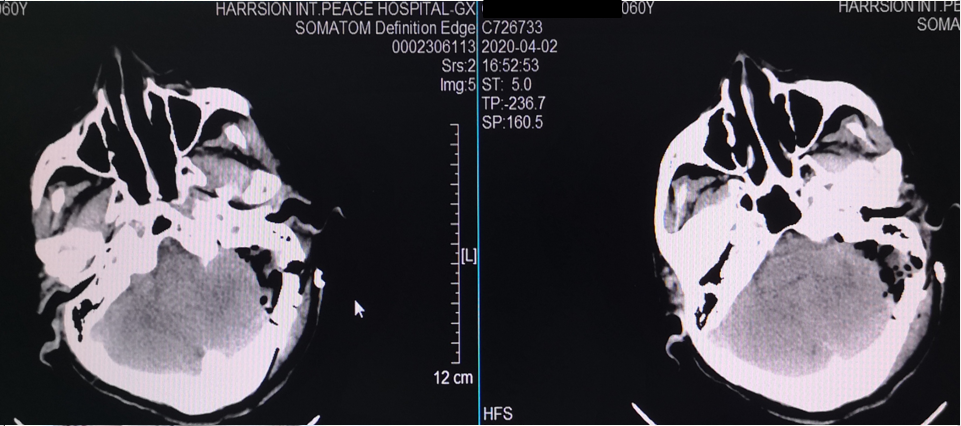

术后复查CT

60岁,女性。左侧面部疼痛8年,加重2月。V1和V2区域电击样疼痛。

MRI示:左侧三叉神经与小脑上动脉关系密切。